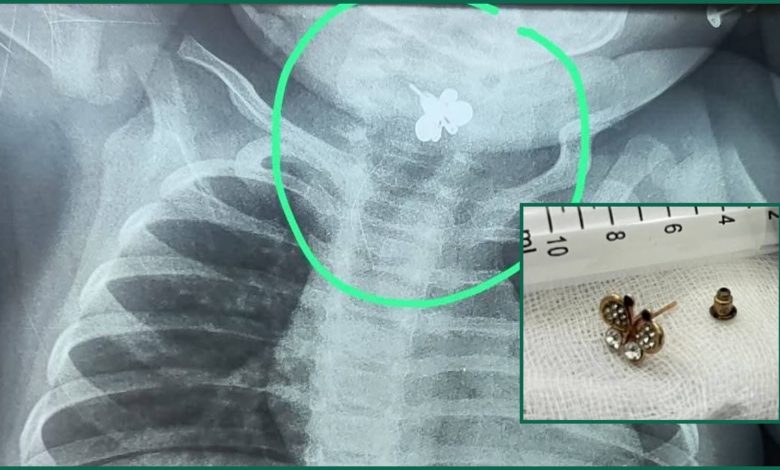

La bebé fue sometida a una radiografía de tórax que permitió observar un objeto extraño. Posteriormente, fue sometida a un procedimiento de extracción en el Instituto Nacional de Enfermedades Respiratorias y del Ambiente (Ineram), que fue todo un éxito. La niña se encuentra internada en estado de observación en la unidad de terapia intermedia.

Síntomas que en principio fueron tratados como una infección urinaria, sin embargo, ante la existencia de los síntomas se ordenó la realización de una radiografía de tórax, lo que reveló la presencia del cuerpo extraño.

“Se observó un objeto extraño metálico en el cuello, en la región cervical. El tiempo transcurrido era ya importante y podía tener secuelas interesantes. Encontramos una inflamación bastante importante, fue dificultoso el procedimiento debido al tiempo que se encontraba ya este arito alojado en la laringe , que no le permitía comer”, expresó el ex ministro de Salud y actual jefe de Endoscopía Respiratoria del Instituto Nacional de Enfermedades Respiratorias y del Ambiente (Ineram), doctor Carlos Morínigo.